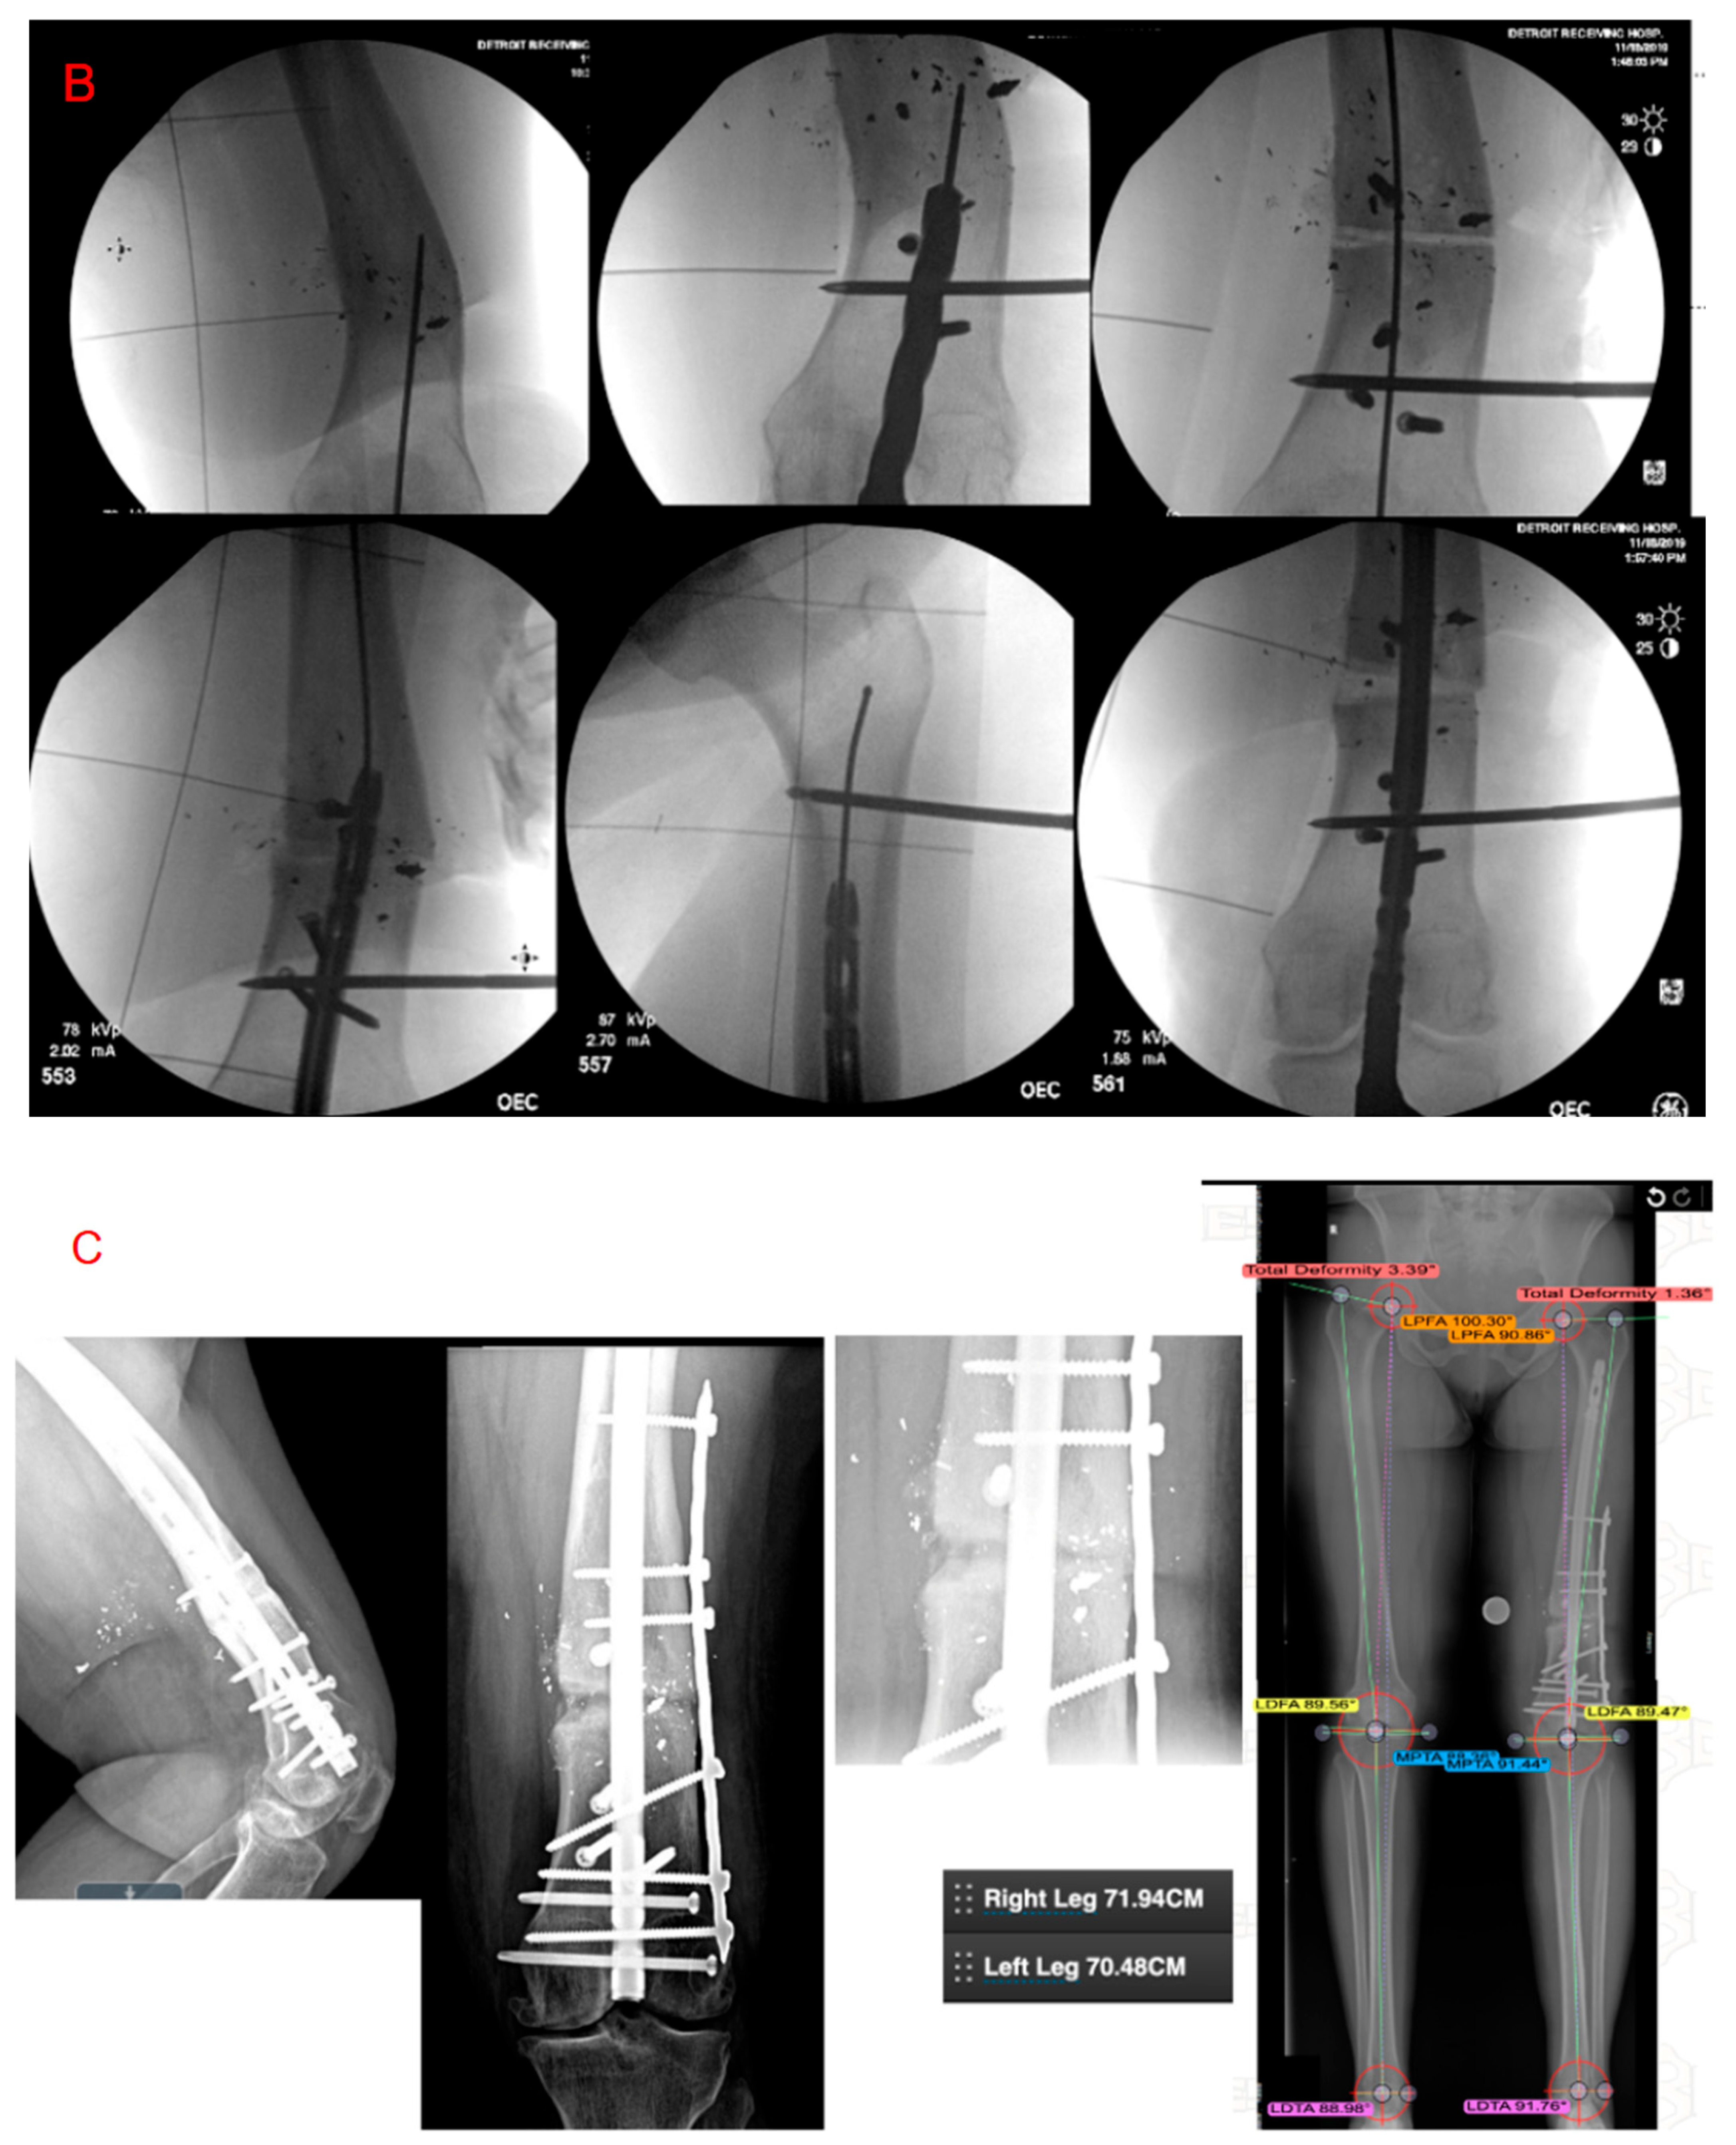

- Vaidya, R.; Dimovski, R.; Cizmic, Z.; Vaidya, A.; Gheraibeh, P.; Hudson, I. Use of Inherent Anteversion of an Intramedullary Nail to Avoid Malrotation in Comminuted Femur Fractures: A Prospective Case–Control Study. J. Orthop. Trauma 2018, 32, 623–628. [Google Scholar] [CrossRef]

- Gheraibeh, P.; Vaidya, R.; Hudson, I.; Meehan, R.; Tonnos, F.; Sethi, A. Minimizing Leg Length Discrepancy After Intramedullary Nailing of Comminuted Femoral Shaft Fractures: A Quality Improvement Initiative Using the Scout Computed Tomography Scanogram. J. Orthop. Trauma 2018, 32, 256–262. [Google Scholar] [CrossRef]